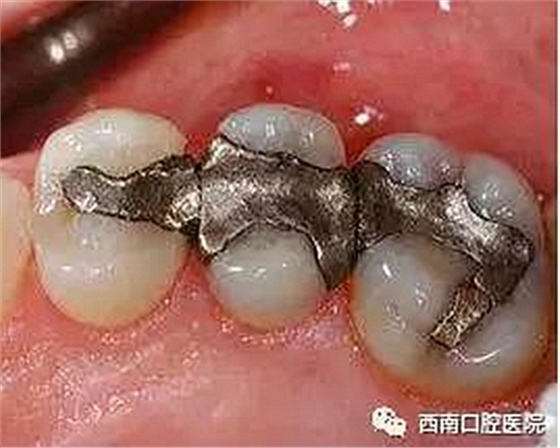

我們來看下各個材料充填之后的顏值吧!

銀汞合金(由銀、錫、汞和其他化合物組成)在牙科安全使用已近150年。但由于其材料長期使用后會有有害成分游離,對身體造成影響,現已逐步被時代舍棄了。